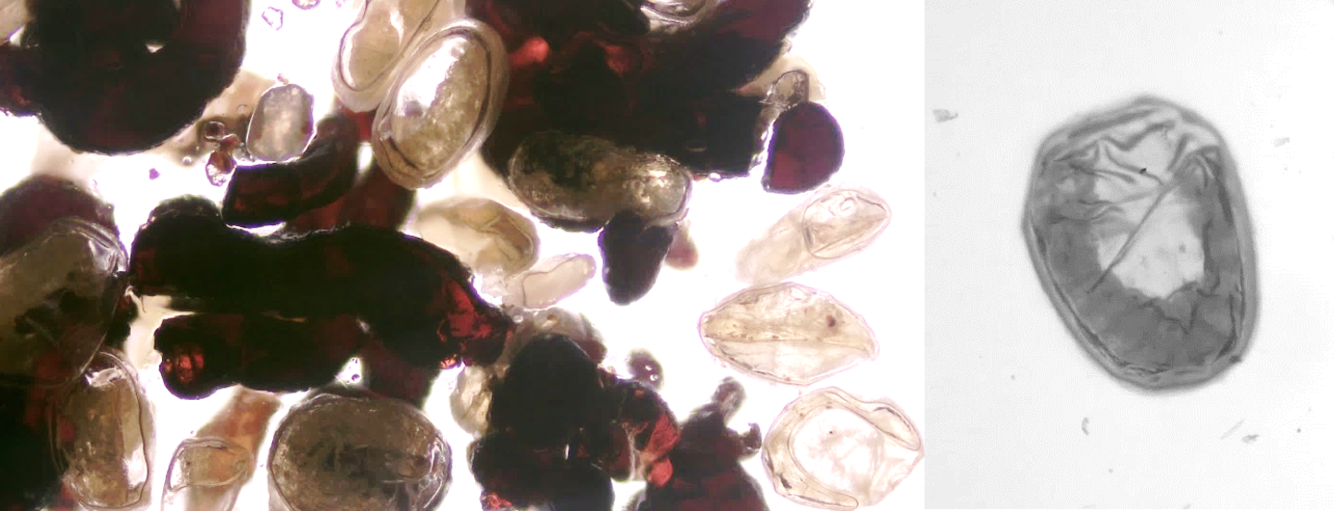

10

Q

identify this parasite

A

dipylidium canium egg

11

toxocara canis egg